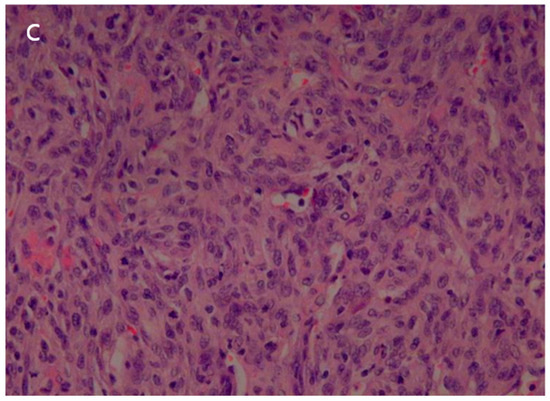

The patient underwent a right upper lobe lobectomy. Gross examination showed a well-circumscribed, pale yellow, soft tumor with hemorrhage, measuring 5.5 × 5.0 cm (Figure 5a). Histopathological analysis revealed a hemangiopericytic growth pattern with areas of coagulation necrosis (Figure 5b). Numerous mitotic figures and marked nuclear pleomorphisms resembled high-grade pleomorphic sarcomas (Figure 5c). Immunohistochemically, the tumor cells were focally positive for CD34 and negative for epithelial markers, such as cytokeratin and EMA (epithelial membrane antigen). Neoplastic cells were negative for desmin, myoglobin, Bcl-2, calretinin, and HMB-45. The immunohistochemical results favored the diagnosis of a malignant solitary fibrous tumor.

Figure 5.

(a) The surgical specimen revealed a well-circumscribed, pale-yellow, soft mass (5.5 cm in diameter) with hemorrhage. (b) Microscopic imaging of the tumor showed a hemangiopericytic pattern and areas of coagulation necrosis (hematoxylin and eosin [HE] × 100). (c) Numerous mitotic figures and marked nuclear pleomorphism were observed in high-grade areas (HE × 400).